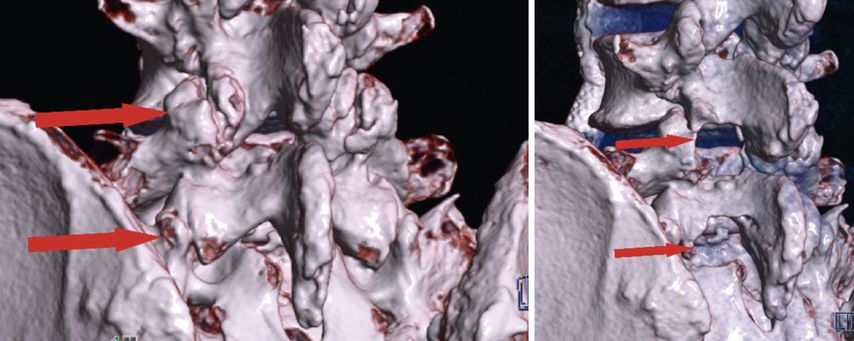

Lumbale vollendoskopische Dekompression

Bei zentraler Spinalkanalstenose und lateraler Rezessusstenose ermöglichen endoskopische Verfahren eine schonende und effektive Dekompression. Eingriffe können unilateral oder bilateral über die Over-the-top-Technik (ULBD) erfolgen. Randomisierte Studien belegen ein funktionell gleichwertiges Outcome im Vergleich zur offenen Dekompression, jedoch bei günstigerem Risikoprofil, kürzerem stationärem Aufenthalt und früherer Mobilisierung.13,19 Bei 161 Patienten mit lateraler Rezessusstenose konnte eine Überlegenheit der vollendoskopischen Operation hinsichtlich Operationszeit, Blutverlust, Komplikationsrate und Revisionshäufigkeit demonstriert werden.19 Am eigenen Patientenkollektiv bei 80 interlaminären vollendoskopischen Dekompressionen konnten 76% der Patienten bereits am Operationstag mobilisiert werden. Über die generellen Vorteile der spinalen Endoskopie hinaus zeigt sich, dass bestimmte Patientengruppen in besonderem Maße profitieren. Hierzu zählen adipöse Patienten, (Leistungs-)Sportler mit dem Bedürfnis nach rascher funktioneller Erholung und minimiertem Gewebetrauma sowie ältere Patienten, bei denen eine erhöhte Invasivität die Mobilisierung weiter einschränken würde und die dadurch profitieren. Abbildung 5 zeigt eine präoperative (linkes Bild) und postoperative (rechtes Bild) 3D-CT-Rekonstruktion nach endoskopischer unilateraler Laminotomie mit bilateraler Dekompression (ULBD) bei L4/5 und L5/S1 (Abb. 5).